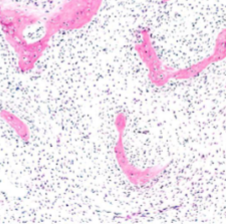

Osteoid Osteoma Morphology

Round to oval well circumscribed mass

Hemorrhagic or tan, gritty tissue

Randomly interconnecting trabeculae of woven bone lined by single layer of osteoblasts with benign features & surrounding stroma with loose connective tissue & dilated capillaries